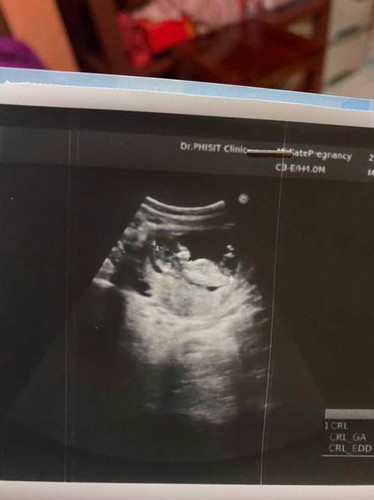

สอบถามแม่ๆหน่อยค่ะ รู้เพศกันกี่เดือนค่ะ บ้านนี้ 13w4dแล้ว พึ่งไปอัลตร้าซาวด์มาวันนี้เห็นน้องแต่ยังไม่ทราบเพศเลยค่ะ อยากรู้เพศแล้ว 😂 แล้วตรวจพบ พาหะธารัสซีเมียอัตรายไหมค่ะ แม่บ้านนี้ตรวจเจอ หมอให้สามีเจาะเลือดด้วยต้องรอฟังผลอีก กังวลมากเลยค่ะ🥲 กลัวจะมีผลกับลูกมากเลยคะ